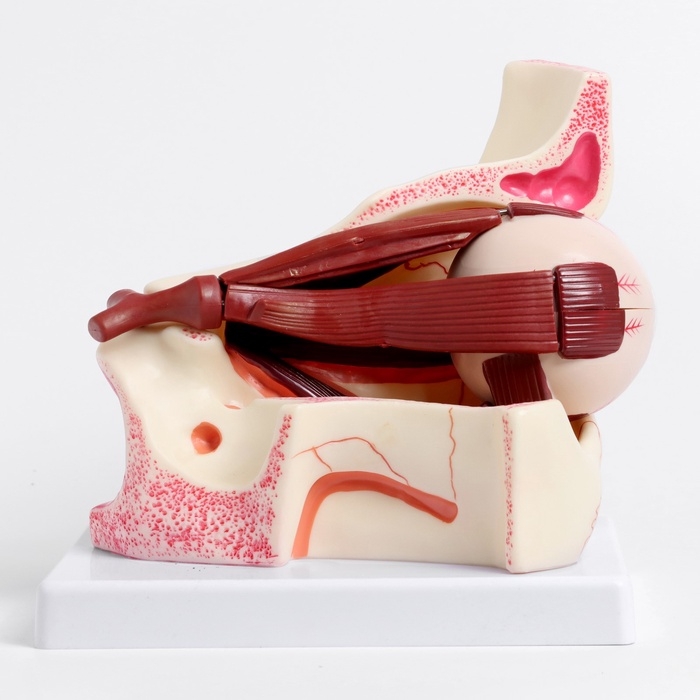

Анатомические модели

ЕКБ 41

No Brand, артикул: 7072360